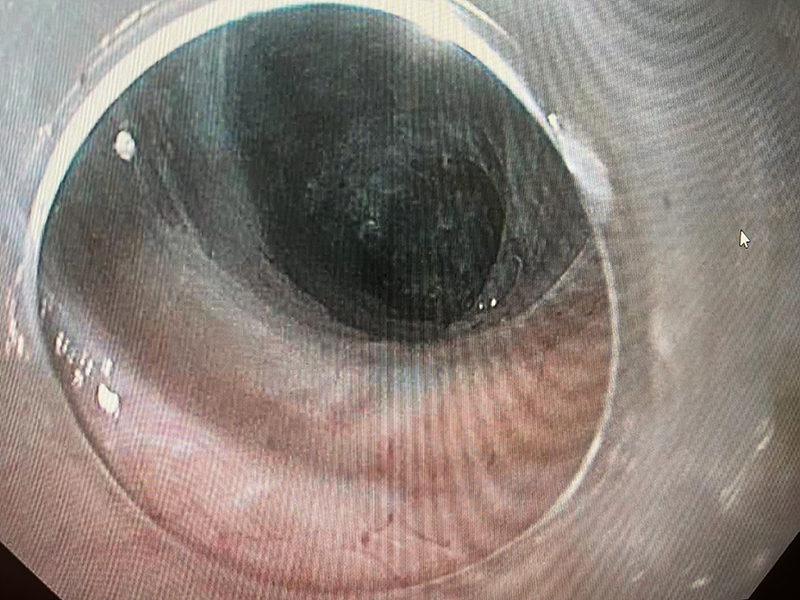

Tunnelling

A long submucosal tunnel of 25cm was created using Speedboat UltraSlim

Inner muscle layer

Frequent manual lifting was achieved with Speedboat UltraSlim's integrated injection delivery